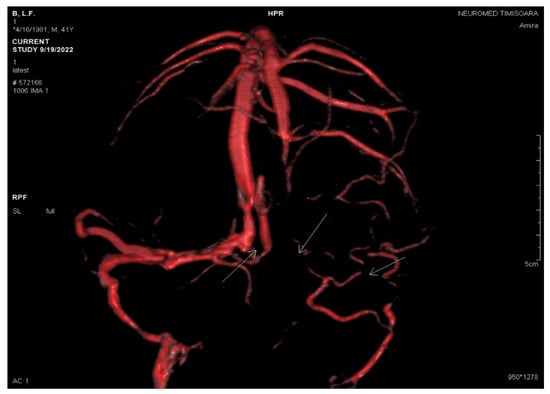

2.2. Neuroimaging Data